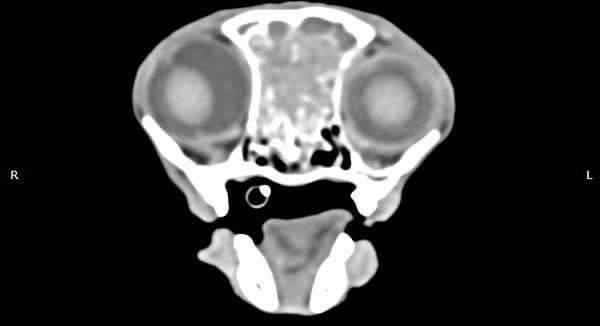

貓咪 鼻腔腫瘤腺癌 Adenocarcinoma

鼻腔腫瘤的診斷需要仰賴電腦斷層掃瞄定位病灶處,同時使用鼻腔內視鏡探查、採樣才能確診,同時有這兩項設備的醫院並不多,所以臨床事並不是那麼容易確診。

貓咪幾個月前開始打噴嚏、流鼻、鼻塞越來越嚴重,他院住院治療改善不佳後轉診至築心檢查。